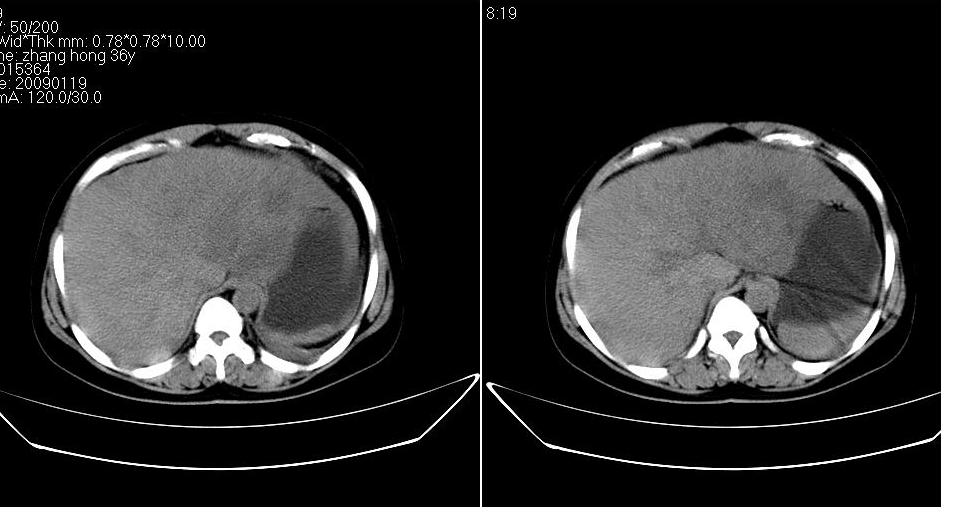

女 36岁,腹痛月余,b超提示肝左叶占位,腹水。

肝脏左叶明显增大,各叶比例失调,左叶实质内不均匀低密度影,增强!